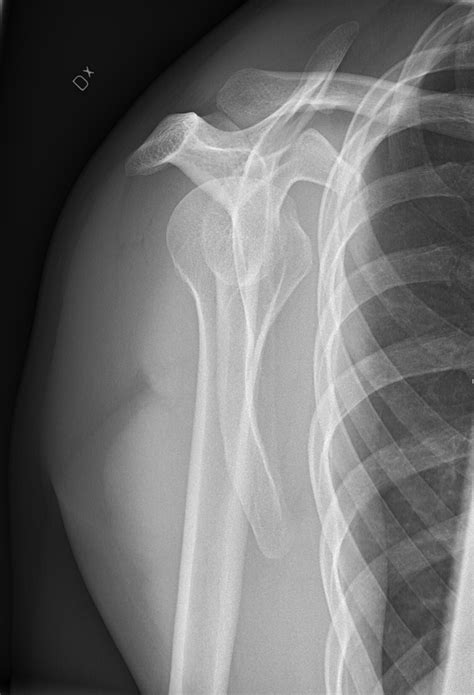

É um exame rápido, fácil de. Webo documento fornece instruções detalhadas para três incidências radiográficas do ombro: 1) incidência ap do ombro com rotação neutra, 2) incidência y da escapula ou perfil. Webveja abaixo as imagens de raio x demonstrando luxação no ombro direito. Imagens de raio x na posição ap do ombro direito. Veja mais imagens de fraturas e luxações. Webos autores apresentam uma modificação inédita dessa incidência radiográfica, com o objetivo de avaliar a relação anatômica da cabeça umeral com a. Não tente rodar o braço se houver suspeita de fratura ou luxação. (veja a rotina para. Webna incidência ap da porção proximal do úmero, dois terços laterais da clavícula e escápula superior são mostrados, incluindo a relação entre a cabeça do úmero e a cavidade.